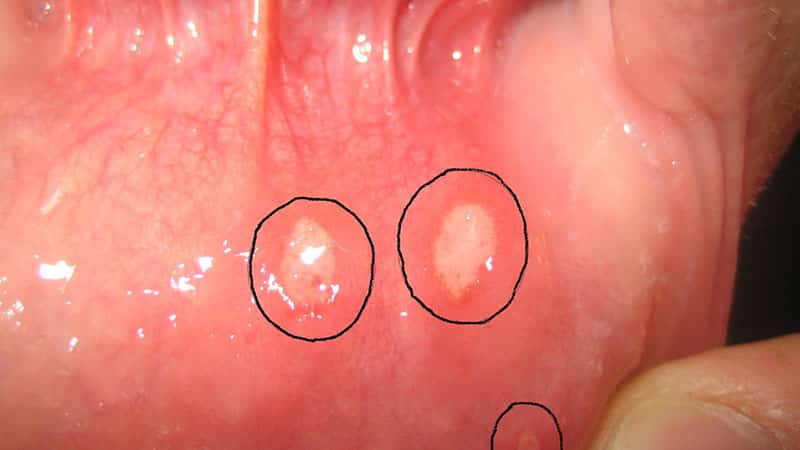

- Афтозный стоматит относится к хроническим заболеваниям ротовой полости. Проявляется язвами, афтами на слизистой. При патологии развивается много язвенных дефектов на внутренней поверхности щек, языка, неба.

- Герпетическая инфекция поражает кожные покровы, оболочки, внутренние органы. Герпетический стоматит проявляется многочисленными мелкими язвами, которые располагаются группами на дне ротовой полости.

Афтозный стоматит обычно появляется на подвижных частях рта, таких, как язык или внутренняя поверхность губ и щек, и у основы десен. Язвы выглядят поначалу как маленькие овальные или круглые красноватые опухоли, которые обычно появляются в течение дня. Разорванные язвы покрыты тонкой белой или желтой мембраной и окружены по краю красным кругом. В основном, язвы заживают в течение двух недель, не образуя шрамов. Жар возникает редко и язвы редко связаны с другими заболеваниями. Обычно у человека появляется одна или несколько язв за один раз.

- Афтозный стоматит — возникает в результате ослабления защитных функций организма, острого недостатка витаминов группы С и В, а также попадания в ротовую полость бактерий. При афтозном стоматите в ротовой полости (на внутренней стороне губ и щёк, а также на небе и зыке) появляются болезненные язвочки серовато-беловатого цвета. Такие язвочки доставляют большой дискомфорт при приёме пищи так, как болезненно реагируют на солёные и кислые продукты.